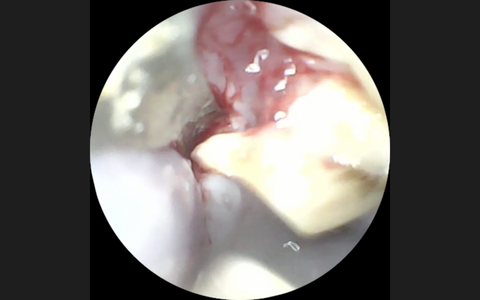

⇩臼歯(奥歯)が不正咬合により過長し、舌や頬の粘膜を傷つけてた症例